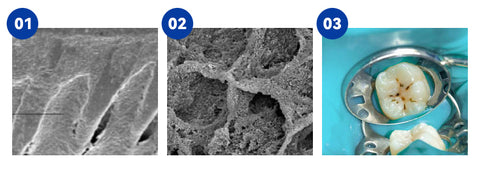

Dental Caries Restoration Process with Oraliz Toothpaste

Image 1: This scanning electron microscope image shows cariogenic bacterial plaque attached to a tooth surface. After 15 days of use, the toothpaste effectively removes this bacterial plaque.

Image 2: This scanning electron microscope image shows a tooth structure affected by caries. Once bacterial plaque is removed, the toothpaste can promote the growth of enamel crystals at a rate of 3-7 microns per day, which can help fill the cavity. With continued use of the toothpaste, the crystals continue to grow.

Image 3: After using the toothpaste for 3-6 months, the enamel crystals can grow up to a thickness of 1-3 millimeters, gradually covering and reducing the cavity, which may help alleviate toothache.